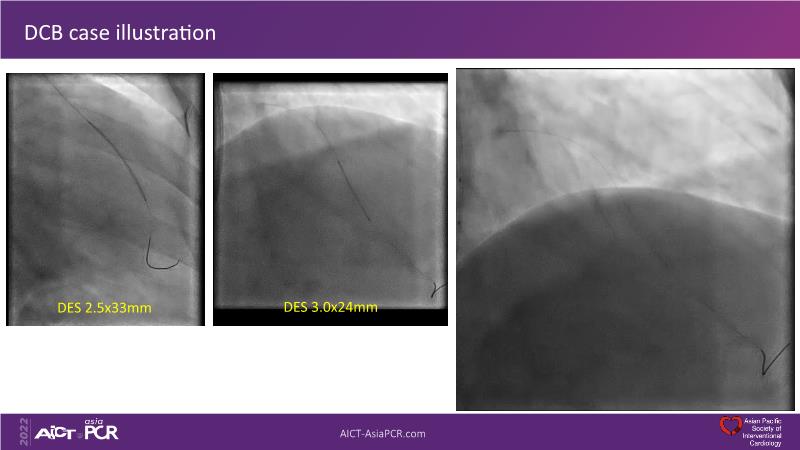

Consult this session to understand the technology and scientific evidence of the novel sirolimus drug-coated balloon, to learn its utility for PCI in a variety of lesion and patient subsets and to understand the evidence and outcomes in real-world patients.

- To understand the technology and scientific evidence of the novel sirolimus drug-coated balloon (SDCB)

- To learn the utility of the DCB for PCI in a variety of lesion and patient subsets

- To understand the evidence and outcomes of this DCB in real world patients